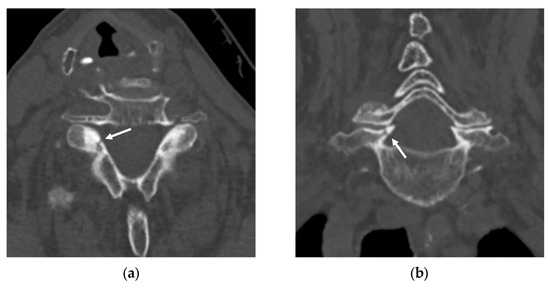

Multicenter, Multinational, and Multivendor Validation of an Artificial Intelligence Application for Acute Cervical Spine Fracture Detection on CT

by Jinkyeong Sung, Peter D. Chang, Angela Ayobi, Martina Cotena, Mar Roca-Sogorb, Jinhee Jang, Daniel S. Chow and Yasmina Chaibi

Diagnostics 2026, 16(2), 194; https://doi.org/10.3390/diagnostics16020194 - 7 Jan 2026

Background/Objectives: While previous studies have evaluated AI algorithms for cervical spine fracture (CSFx) detection on CT, many have lacked validation on diverse, multinational datasets or have focused primarily on overall case-level classification This study aimed to evaluate the performance of an AI application [...] Read more.

Background/Objectives: While previous studies have evaluated AI algorithms for cervical spine fracture (CSFx) detection on CT, many have lacked validation on diverse, multinational datasets or have focused primarily on overall case-level classification This study aimed to evaluate the performance of an AI application for acute CSFx detection in case-level classification, fracture localization, and spinal level labeling on multicenter, multinational, and multivendor CT data. Methods: Non-enhanced CTs were retrospectively collected from a U.S. teleradiology company, a French teleradiology company, and a U.S. university hospital. Four radiologists independently labeled the presence and location (including the spinal level) of acute CSFx to establish the reference standard. Per-case diagnostic performance, per-bounding box positive predictive value (PPV) for localization, and overall agreement of cervical vertebral level labeling of the AI were assessed. Results: A total of 155 patients (60.6 years ± 21.2 years, 104 men) with acute CSFx and 173 patients (51.9 years ± 22.7 years, 91 men) without acute CSFx were evaluated. Data were acquired using scanners from five manufacturers. For acute CSFx diagnosis, the AI achieved a per-case sensitivity of 90.3%, a specificity of 91.9%, an accuracy of 91.2%, an area under the receiver operating characteristic curve (AUC) of 0.91, and Matthews correlation coefficient of 0.82. Among 192 bounding boxes representing acute CSFx generated for 154 positive cases by the AI, 162 were true positives (per-bounding box PPV, 84.4%). Of the 186 bounding boxes for which the AI displayed cervical spinal level, 181 were labeled correctly (overall agreement, 97.3%). Conclusions: The AI application for detecting acute CSFx demonstrated high diagnostic performance on multicenter, multinational, and multivendor data, with high performance in fracture localization and spinal level labeling. Full article

(This article belongs to the Special Issue Contemporary Spine Diagnostics and Management)

Show Figures

Figure 1